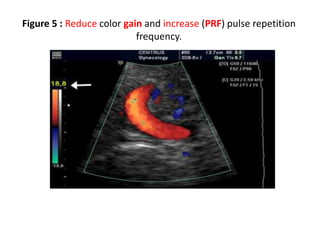

Figure (4 & 5) slides (7/8)

Figure 4 : Aliasing of color doppler imaging and artefacts of color.

Color image shows regions of aliased flow (yellow arrows).

Figure 5 : Reduce color gain and increase (PRF) pulse repetition

frequency.